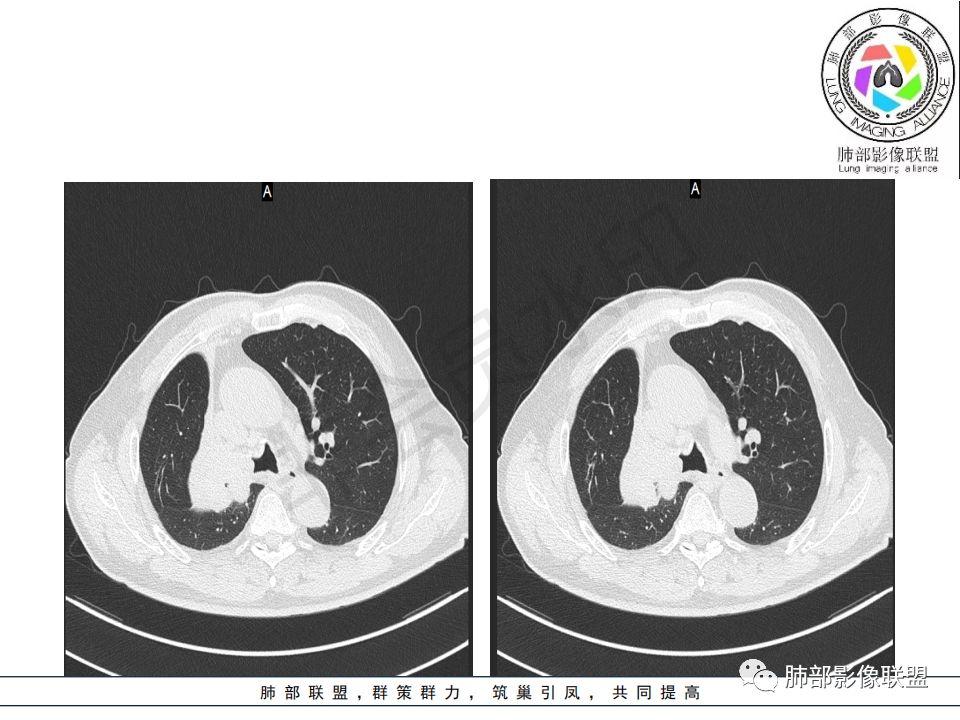

病史:男.77岁,咳嗽1月;干咳,少许白痰,无发热,2013胃癌术后,角蛋白24.65(0-3.07),SCC和proGRP不高;

影像:影像右侧大支气管阻塞,临床没有症状或很轻微,要想到胃腺癌转移;胸壁代偿好,透亮度稍低不明显,慢性过程;34.8-52.5HU,主病灶支气管前壁另有1结节,都做成增强两期了,动脉期较平扫有强化;

诊断:多发,转移,无淋巴结及胸腔积液;

鉴别:原发鳞癌。

晨读:患者老年男性,以咳嗽一月就诊,少量白痰,胸CT:纵隔右移,右肺体积缩小,气管下段管壁可见结节样改变,气管软骨变形,气管下段及右主支气管可见新生物向管壁浸润,并向管腔外生长,右上肺肺不张,但不张边缘可见病灶呈膨胀性生长,可见分叶,增强后强化明显。考虑:肺部恶性病变(鳞癌?)

1.右肺上叶较大块影,密度不均,轻度强化并见低密度区,所属支气管截断并腔内突入,是符合肺鳞癌的影像学特征和生物学行为的。